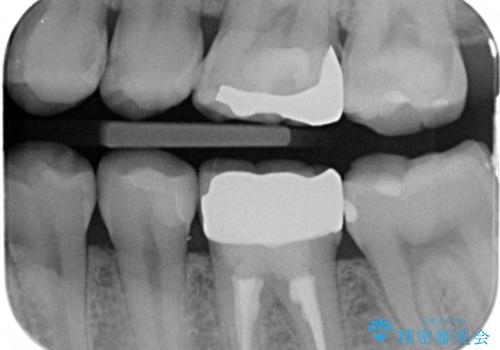

レントゲンで診査したら、歯と歯の間に虫歯(コンタクトカリエス)が見られたので

e-maxインレーで治療を行いました。

- e-maxインレー 7.7万円 ×2本費用は治療当時の料金となります